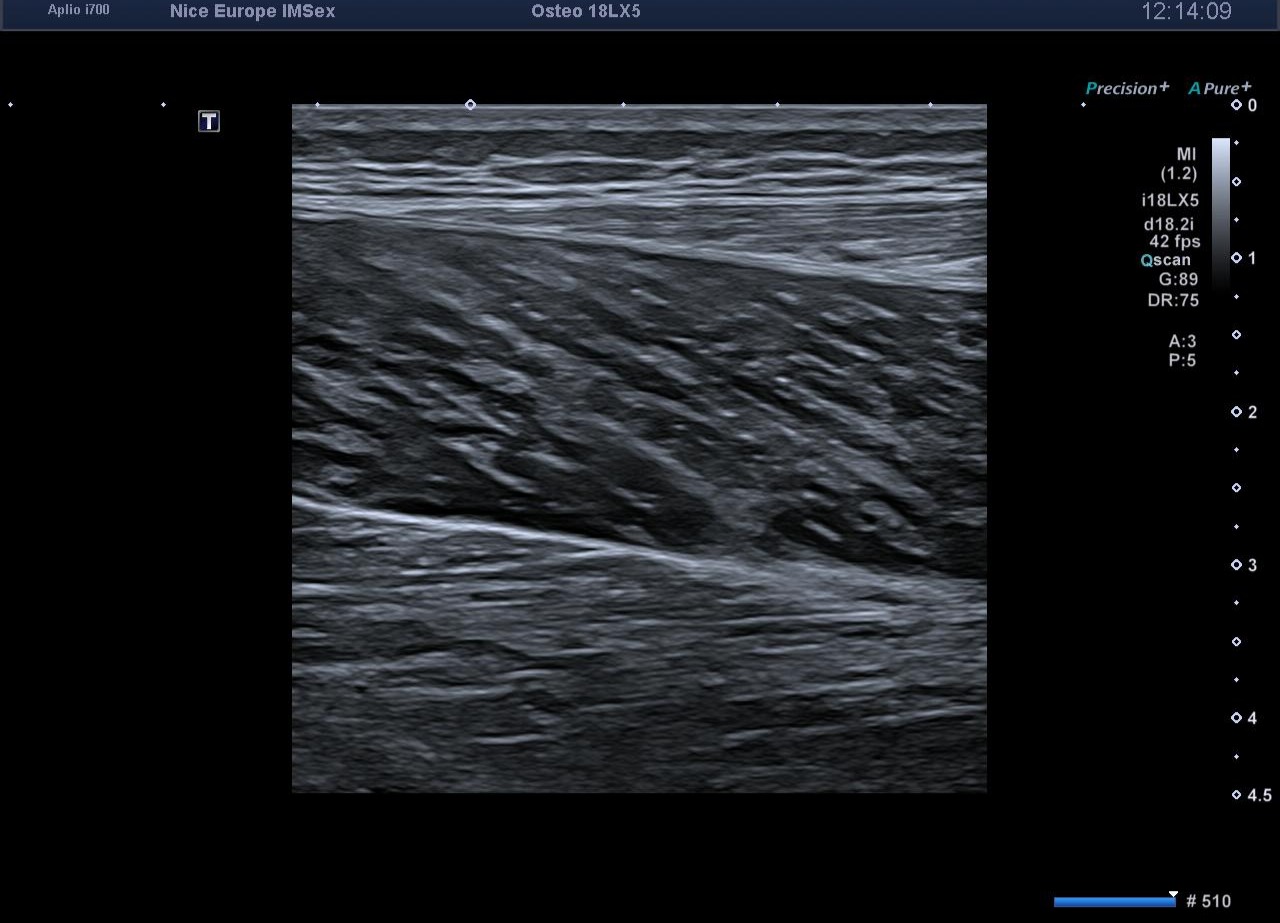

L’exploration statique haute résolution de la cheville et du mollet s'avère strictement normale. Les tendons calcanéens (d'Achille) présentent une écho-structure fibrillaire parfaitement conservée, sans épaississement focal, ni hyperhémie au Doppler énergie. L'exploration de la loge postérieure montre des ventres musculaires gastrocnémiens et soléaires volumineux mais d'échostructure normale, tout comme les jonctions myo-aponévrotiques. L'artère poplitée est perméable au repos, avec un flux Doppler triphasique physiologique.

À ce stade, l'examen clinique, obligatoirement réalisé de manière concomitante à l'exploration échographique, prend tout son sens. La palpation minutieuse des loges musculaires et la parfaite intégrité des tendons obligent l'opérateur à s'écarter de la prescription initiale pour rechercher une étiologie vasculaire à cette symptomatologie d'effort.